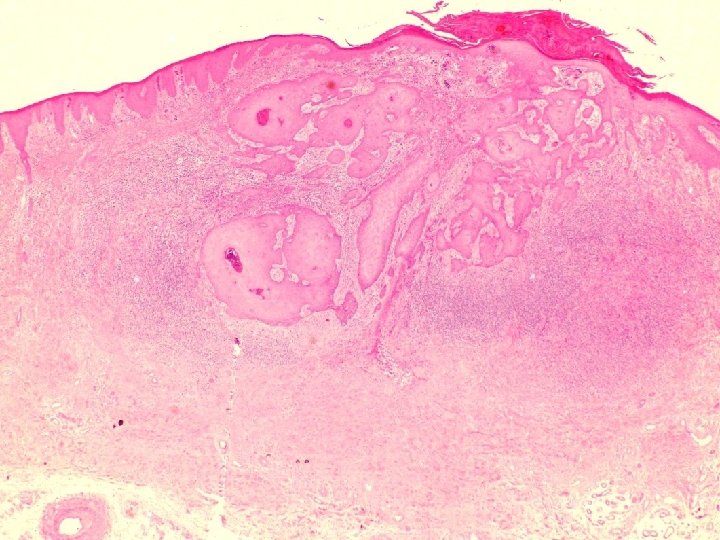

�Case number: 191 �Male aged 60 years. �Skin left popliteal fossa excision. Five week

�Case number: 191 �Male aged 60 years. �Skin left popliteal fossa excision. Five week history of nodule on skin. No pus. Has some insect bites. ? insect bite reaction, ? keratoacanthoma versus SCC. �Macro: Skin biopsy 18 x 13 x 2 mm in depth with a centrally raised slightly keatotic lesion 5 mm in diameter.